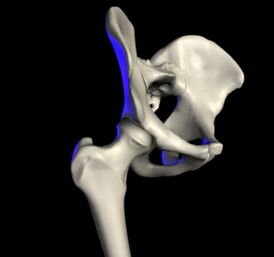

Компьютерная модель сустава.

Та́зобе́дренный суста́в (лат. articulátio cóxae) — чашеобразный, многоосный сустав, образованный полулунной поверхностью вертлужной впадины тазовой кости и суставной поверхностью головки бедренной кости. Вертлужная губа, сращённая с краем вертлужной впадины, углубляет последнюю.